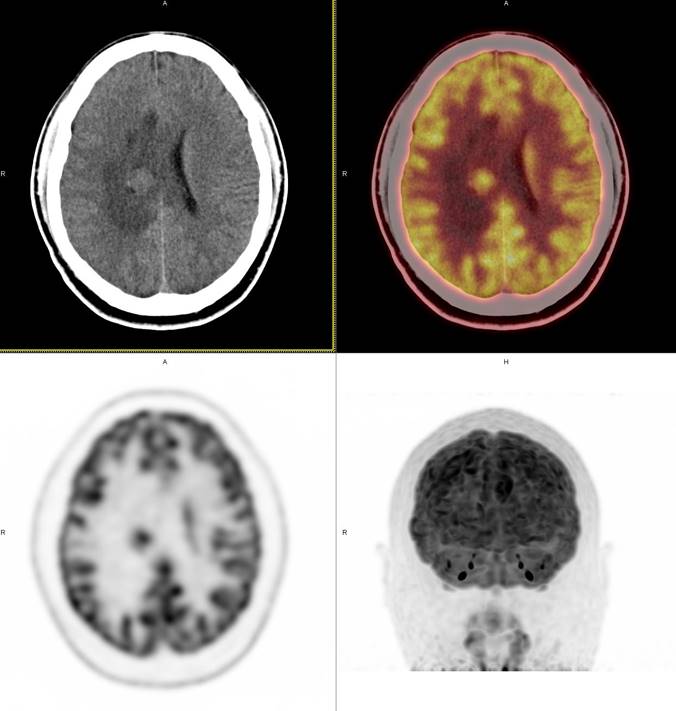

PET/CT影像圖

圖1

圖2

圖3

圖4

PET/CT檢查

影像診斷: 右側(cè)側(cè)腦室旁腦實(shí)質(zhì)內(nèi)結(jié)節(jié),代謝異常增高(SUVmax 12.13),伴瘤周水腫。

病理診斷:腦膜瘤二級(jí)